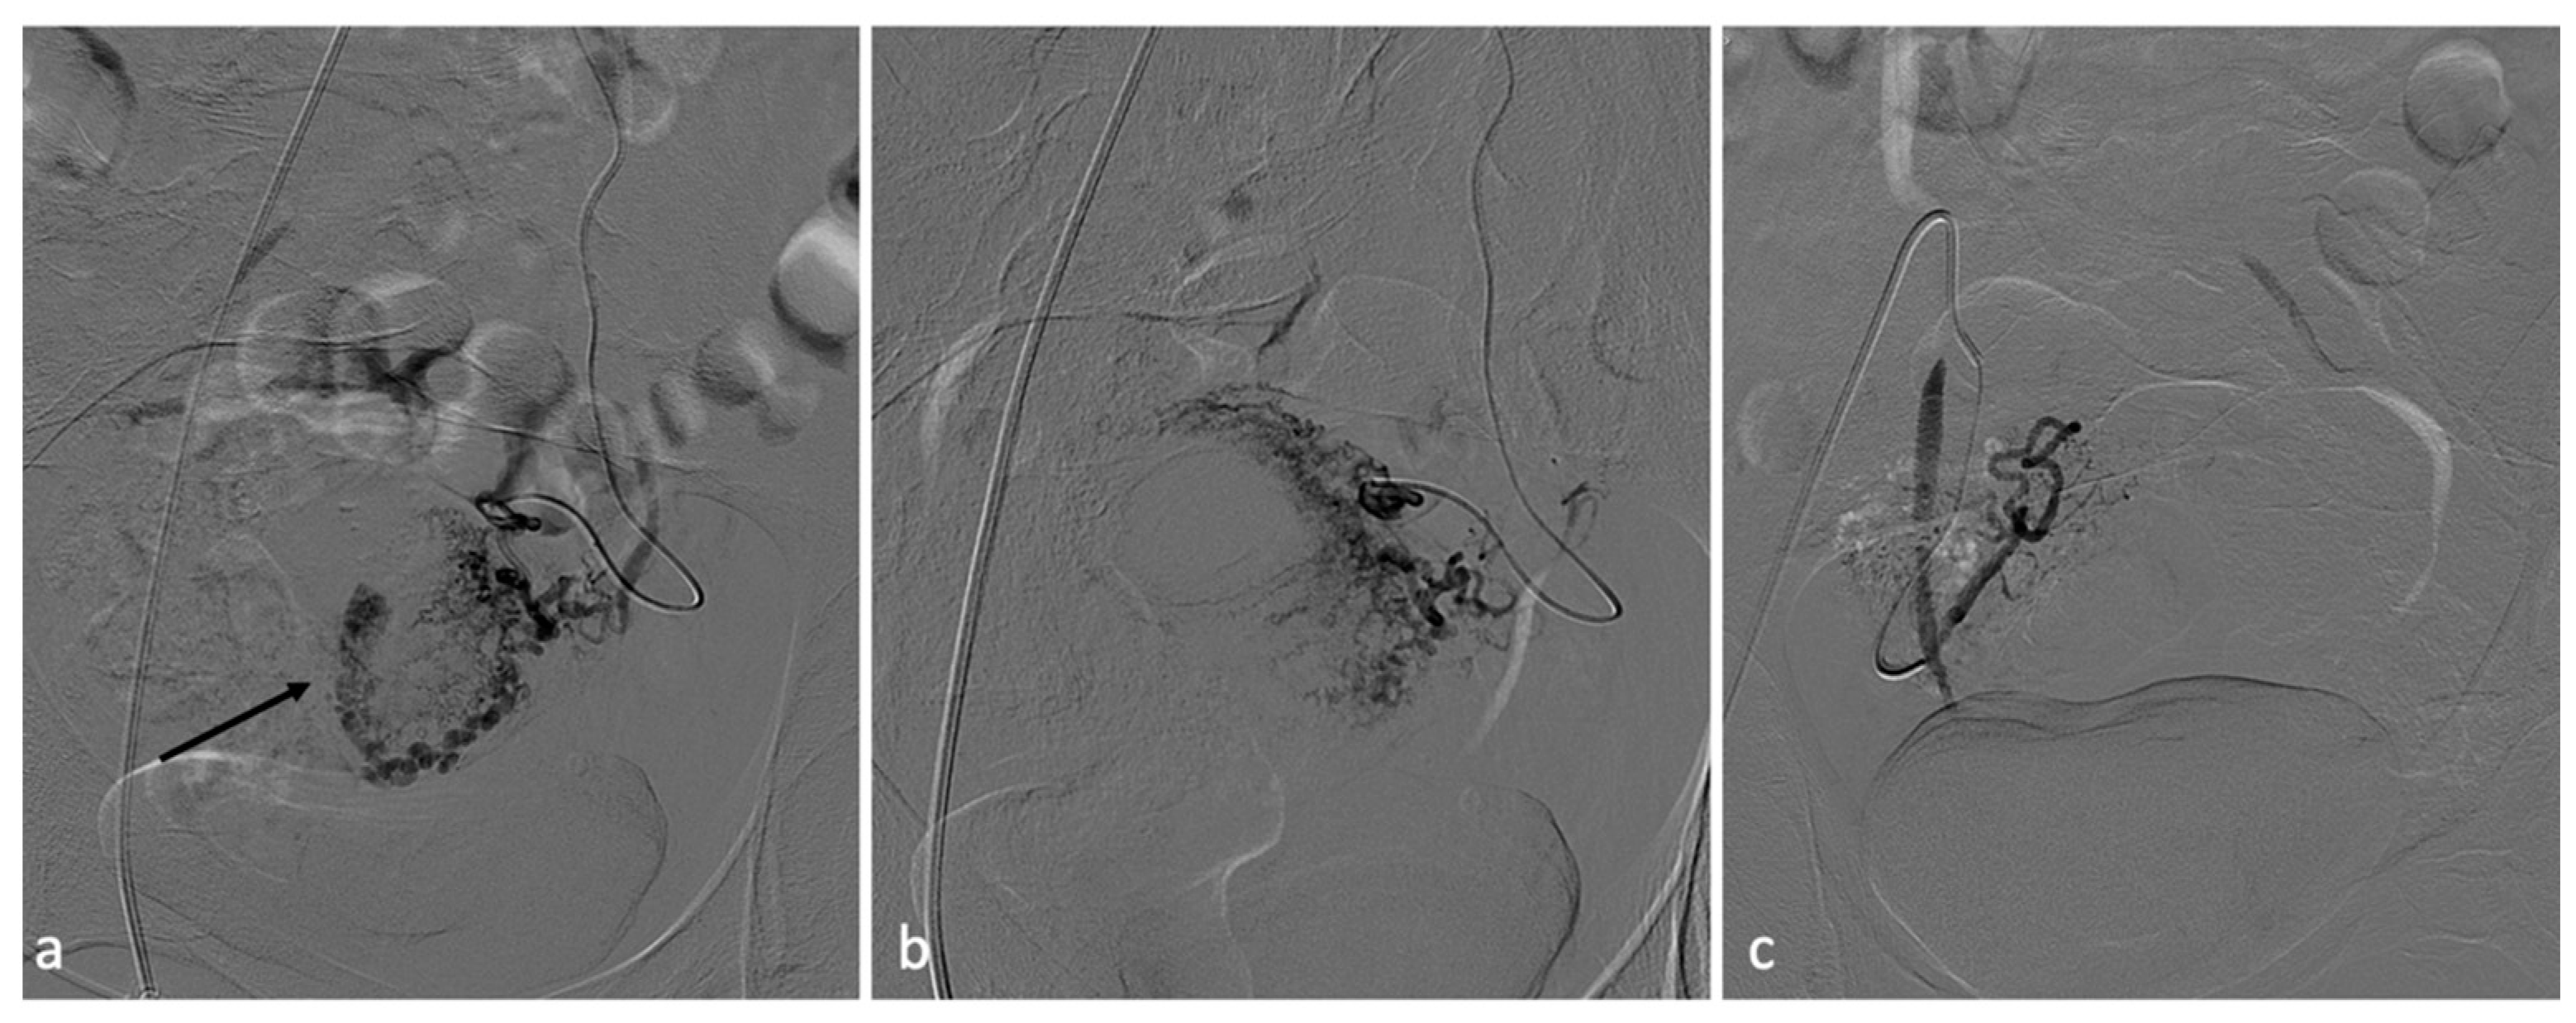

Figure 10.

RPOC. A 25-year-old patient who continued to experience vaginal bleeding 1 month after natural birth. Ultrasound performed at another center howed the presence of placental residue suspicious for accreted succenturiate cotyledon. It was, therefore, decided to perform an embolization procedure. Bilateral hypogastric angiography documented the presence of hypervascular formation in the central portions of the uterus (a). After superselective coaxial microcatheterization of the uterine arteries, they were embolized with absorbable material (b). Control angiography documented effective vascularization of the lesion (c).